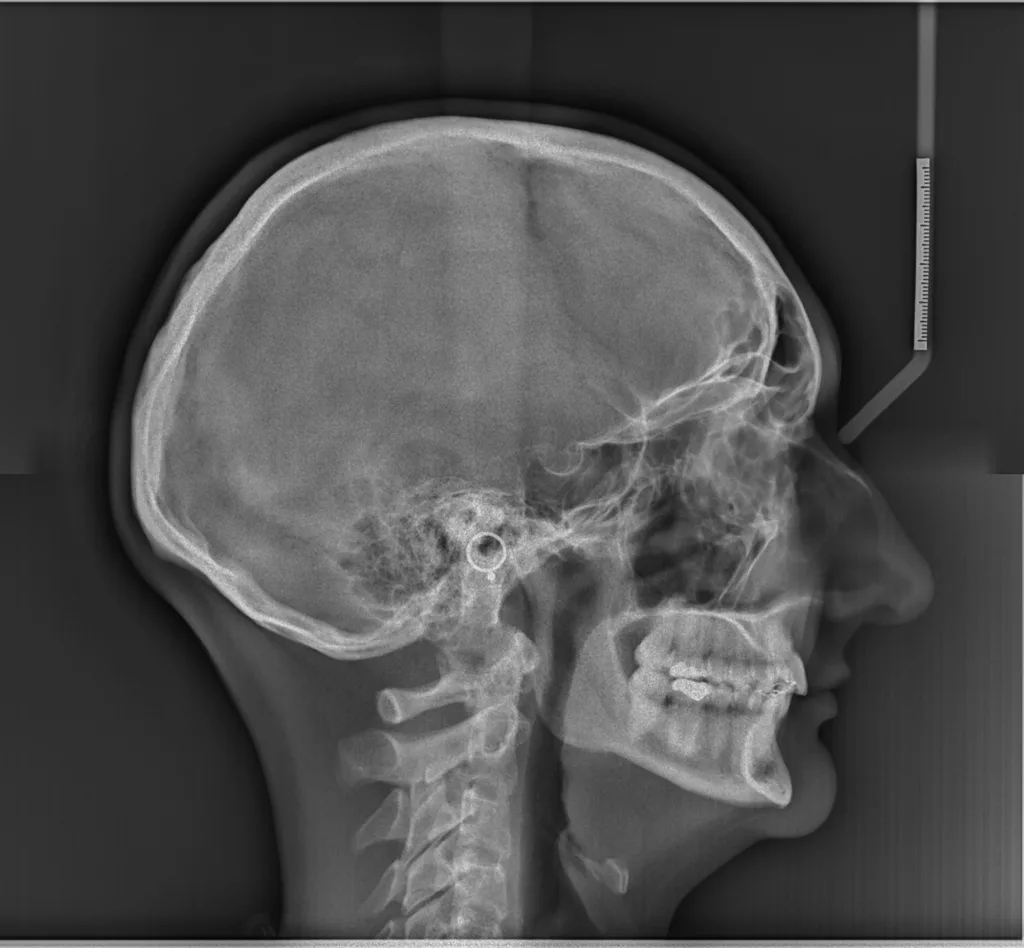

Parmi les examens radiographiques nécessaires, les radiographies de profil et de face correctement orientées et contenant l’ensemble de la tête (sommet du crâne inclus) sont particulièrement importantes. Ces radiographies correctement effectuées permettent d’établir une véritable cartographie du squelette du patient et en conséquence de comprendre sa malformation. Cette analyse cartographique du squelette a pour nom « céphalométrie ». De nombreux types d’analyses céphalométriques existent et sont utilisées selon les pays et universités. Parmi elles, l’analyse céphalométrique architecturale et structurale de Jean Delaire tient une place particulière.

L’Analyse Céphalométrique architecturale et structurale de Jean Delaire

L’analyse céphalométrique architecturale crânio-faciale de Jean Delaire, à la différence des autres méthodes d’analyse qui sont principalement basées sur des moyennes statistiques définissant ce qui est « normal » et ce qui est « anormal » (c’est à dire pathologique) est basée sur la notion d’équilibre ou de déséquilibre architectural du squelette crânio-facial propre à chaque individu en tenant compte des principaux appareils anatomiques à son contact et des principales fonctions qui interfèrent avec lui. « A l’état d’équilibre, tous les éléments de l’extrémité céphalique ; squelette et tissus mous sont et fonctionnent en parfait équilibre mutuel ».

Pour chaque individu, l’analyse architecturale crânio-faciale de Jean Delaire permet de déterminer « l’équilibre » squelettique idéal qui lui est propre c’est-à-dire « sa normalité » et de constater, s’il existe, l’état de «déséquilibre » dans lequel il se trouve, c’est-à-dire l’état « pathologique » dans lequel il se trouve en tenant compte de son âge, de ses antécédents personnels ou familiaux, de son état fonctionnel ou dysfonctionnel, de l’existence d’éventuelles pathologies associées.

Pour chaque patient étudié l’analyse céphalométrique de Jean Delaire permet de :

- Connaître et de quantifier le morphotype qui lui est propre

- Analyser la situation d’équilibre (la normalité) ou de déséquilibre (la situation pathologique) dans laquelle se trouve l’ensemble de son extrémité céphalique ; crâne, massif facial et rachis cervical (analyse architecturale),

- Déterminer la participation respective de chaque élément anatomique dans la malformation ; maxillaire, mandibule, os basal, os alvéolaire, dents (analyse orthognathique et dentaire),

- Evaluer l’anomalie de position de chacune des pièces et unités anatomiques et de connaitre la position qu’elles auraient dû avoir en l’absence de pathologie guidant ainsi au mieux le chirurgien dans son plan de traitement chirurgical (analyse topographique)

L’analyse architecturale est complétée par l’analyse structurale. Pour chaque patient elle consiste à examiner attentivement tous la « structure » de l’extrémité céphalique c’est dire l’anatomie de chacune des pièces squelettiques et des parties molles qui la compose pour mieux comprendre le mécanisme d’installation et d’entretien de la dysmorphose. En association avec l’analyse architecturale elle permet de poser le diagnostic le plus précis afin de choisir le meilleur traitement chirurgical et orthodontique.